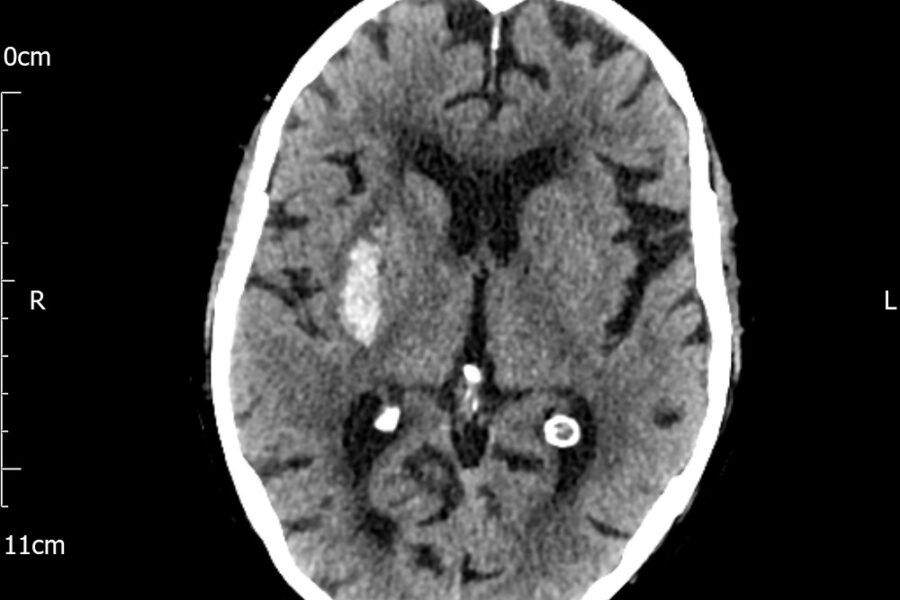

- Anatomy and Pathology in Cross-Sectional Imaging